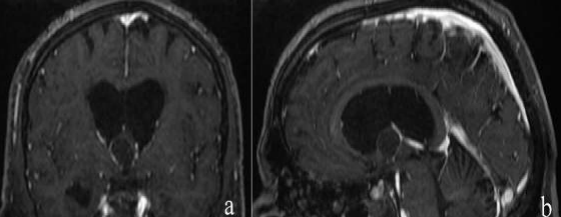

During his admission, he was awake, without major deficit However, we noticed slight recent memory disorders, otherwise he didn’t present a motor deficit in his four limbs. Considering his history of raised intracranial pressure, we have performed an eye fundus that was normal as well as the rest of the ophthalmological evaluation .A brain CT scan showed an isodense lesion, in the midline close to Monroe’s foramina There was a  passive ventriculomegaly. In the MRI, the cyst appeared to be isointense in T1 sequences and hyperintense in T2. The anterior insertion of the cyst was close to the foramen of Monro. There was a passive hydrocephalus. (Figure 1).

Figure 1: Preoperative MRI: a- coronal T1 + contrast showing an isointense cyst projecting through the foramen of Monro with the venous system dropped over the edges of the cyst. b- sagittal T1 + contrast showing the position of the cyst and the interventricular foramina and the internal cerebral vein. a ventriculomegaly could be noticed favoring our transventriuclar approach.